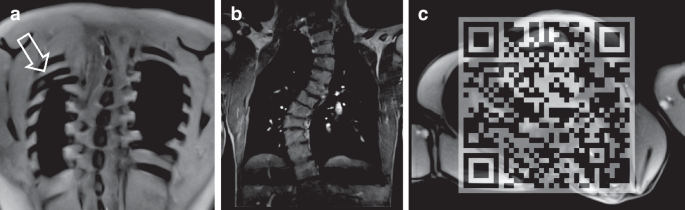

Adult EA patients exhibited significantly more rib adhesions (12/30, 40%) and rib fusions (15/30, 50%) compared to healthy controls (p < 0.01 and p < 0.001, respectively; Table 1 and Fig. 1a). All abnormalities were located on the right side, predominantly involving ribs 3, 4, or 5.

a Fusion of Rib 4 and 5 (arrow) and b scoliosis in a 29- and 27-year-old patient, respectively, following open EA repair. c Real-Time MRI of a patient with severe vertebral and chest wall anomaly in 20-year-old EA patient. (https://pedz.de/supplementals/ea-adult/video1.mp4).

Scoliosis was observed in 13/30 (43.3%) EA patients (p < 0.01; Table 1 and Fig. 1b). Among these, 6/13 (46%) had grade I scoliosis (<25°), while 4/13 (31%) had moderate grade II scoliosis (25°–40°), and 3/13 (23%) had severe grade III scoliosis (>40°). One patient presented with a butterfly-shaped vertebral body in the mid-thoracic spine, along with severe left hemithorax deformity characterized by a 180° rib rotation and severe scoliosis, despite multiple spine distractions and implantation of a vertical expandable prosthetic titanium rib device (Fig. 1c). No other patient underwent surgical intervention for scoliosis of chest wall deformity.